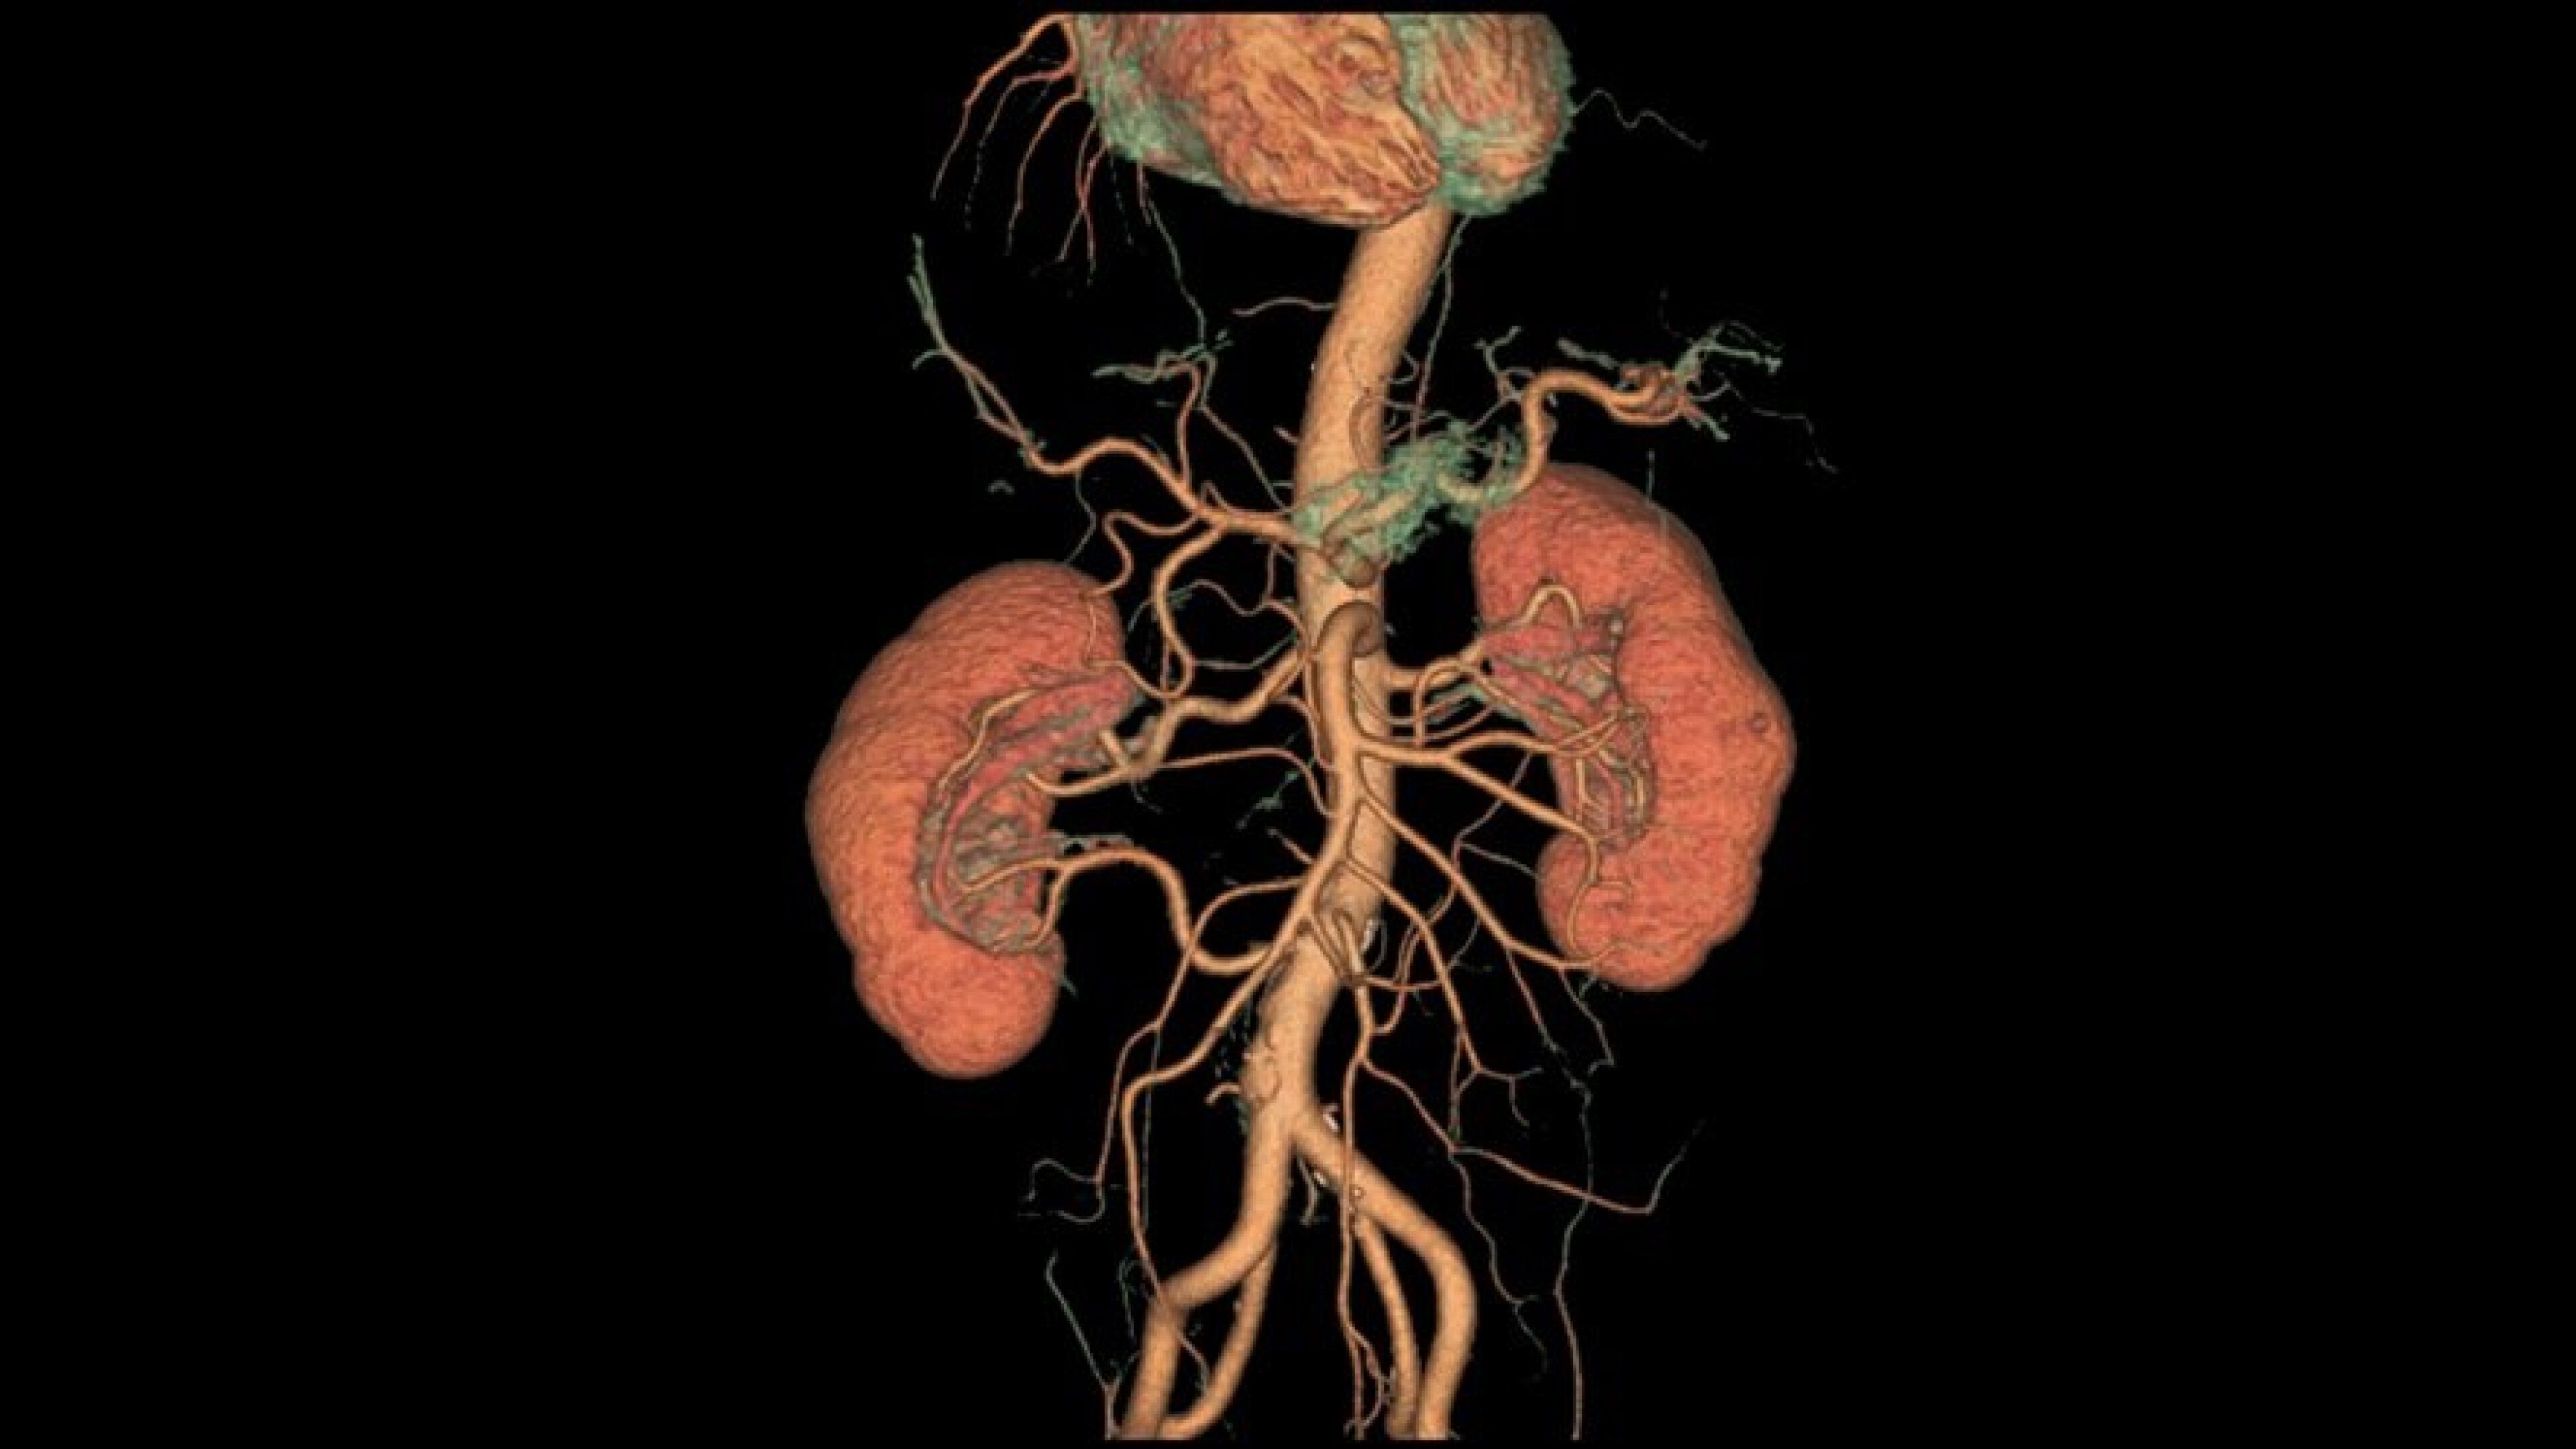

Autobone & VesselIQ Xpress

Fast and efficient vessel analysis from CT Angiography exams.

Automated detection of aorta and illiacs with auto-labeling of vessels

Comprehensive stenosis measurement and plaque analysis of any vasculature

• Automated detection of aorta an illiacs with auto labeling of vessels.